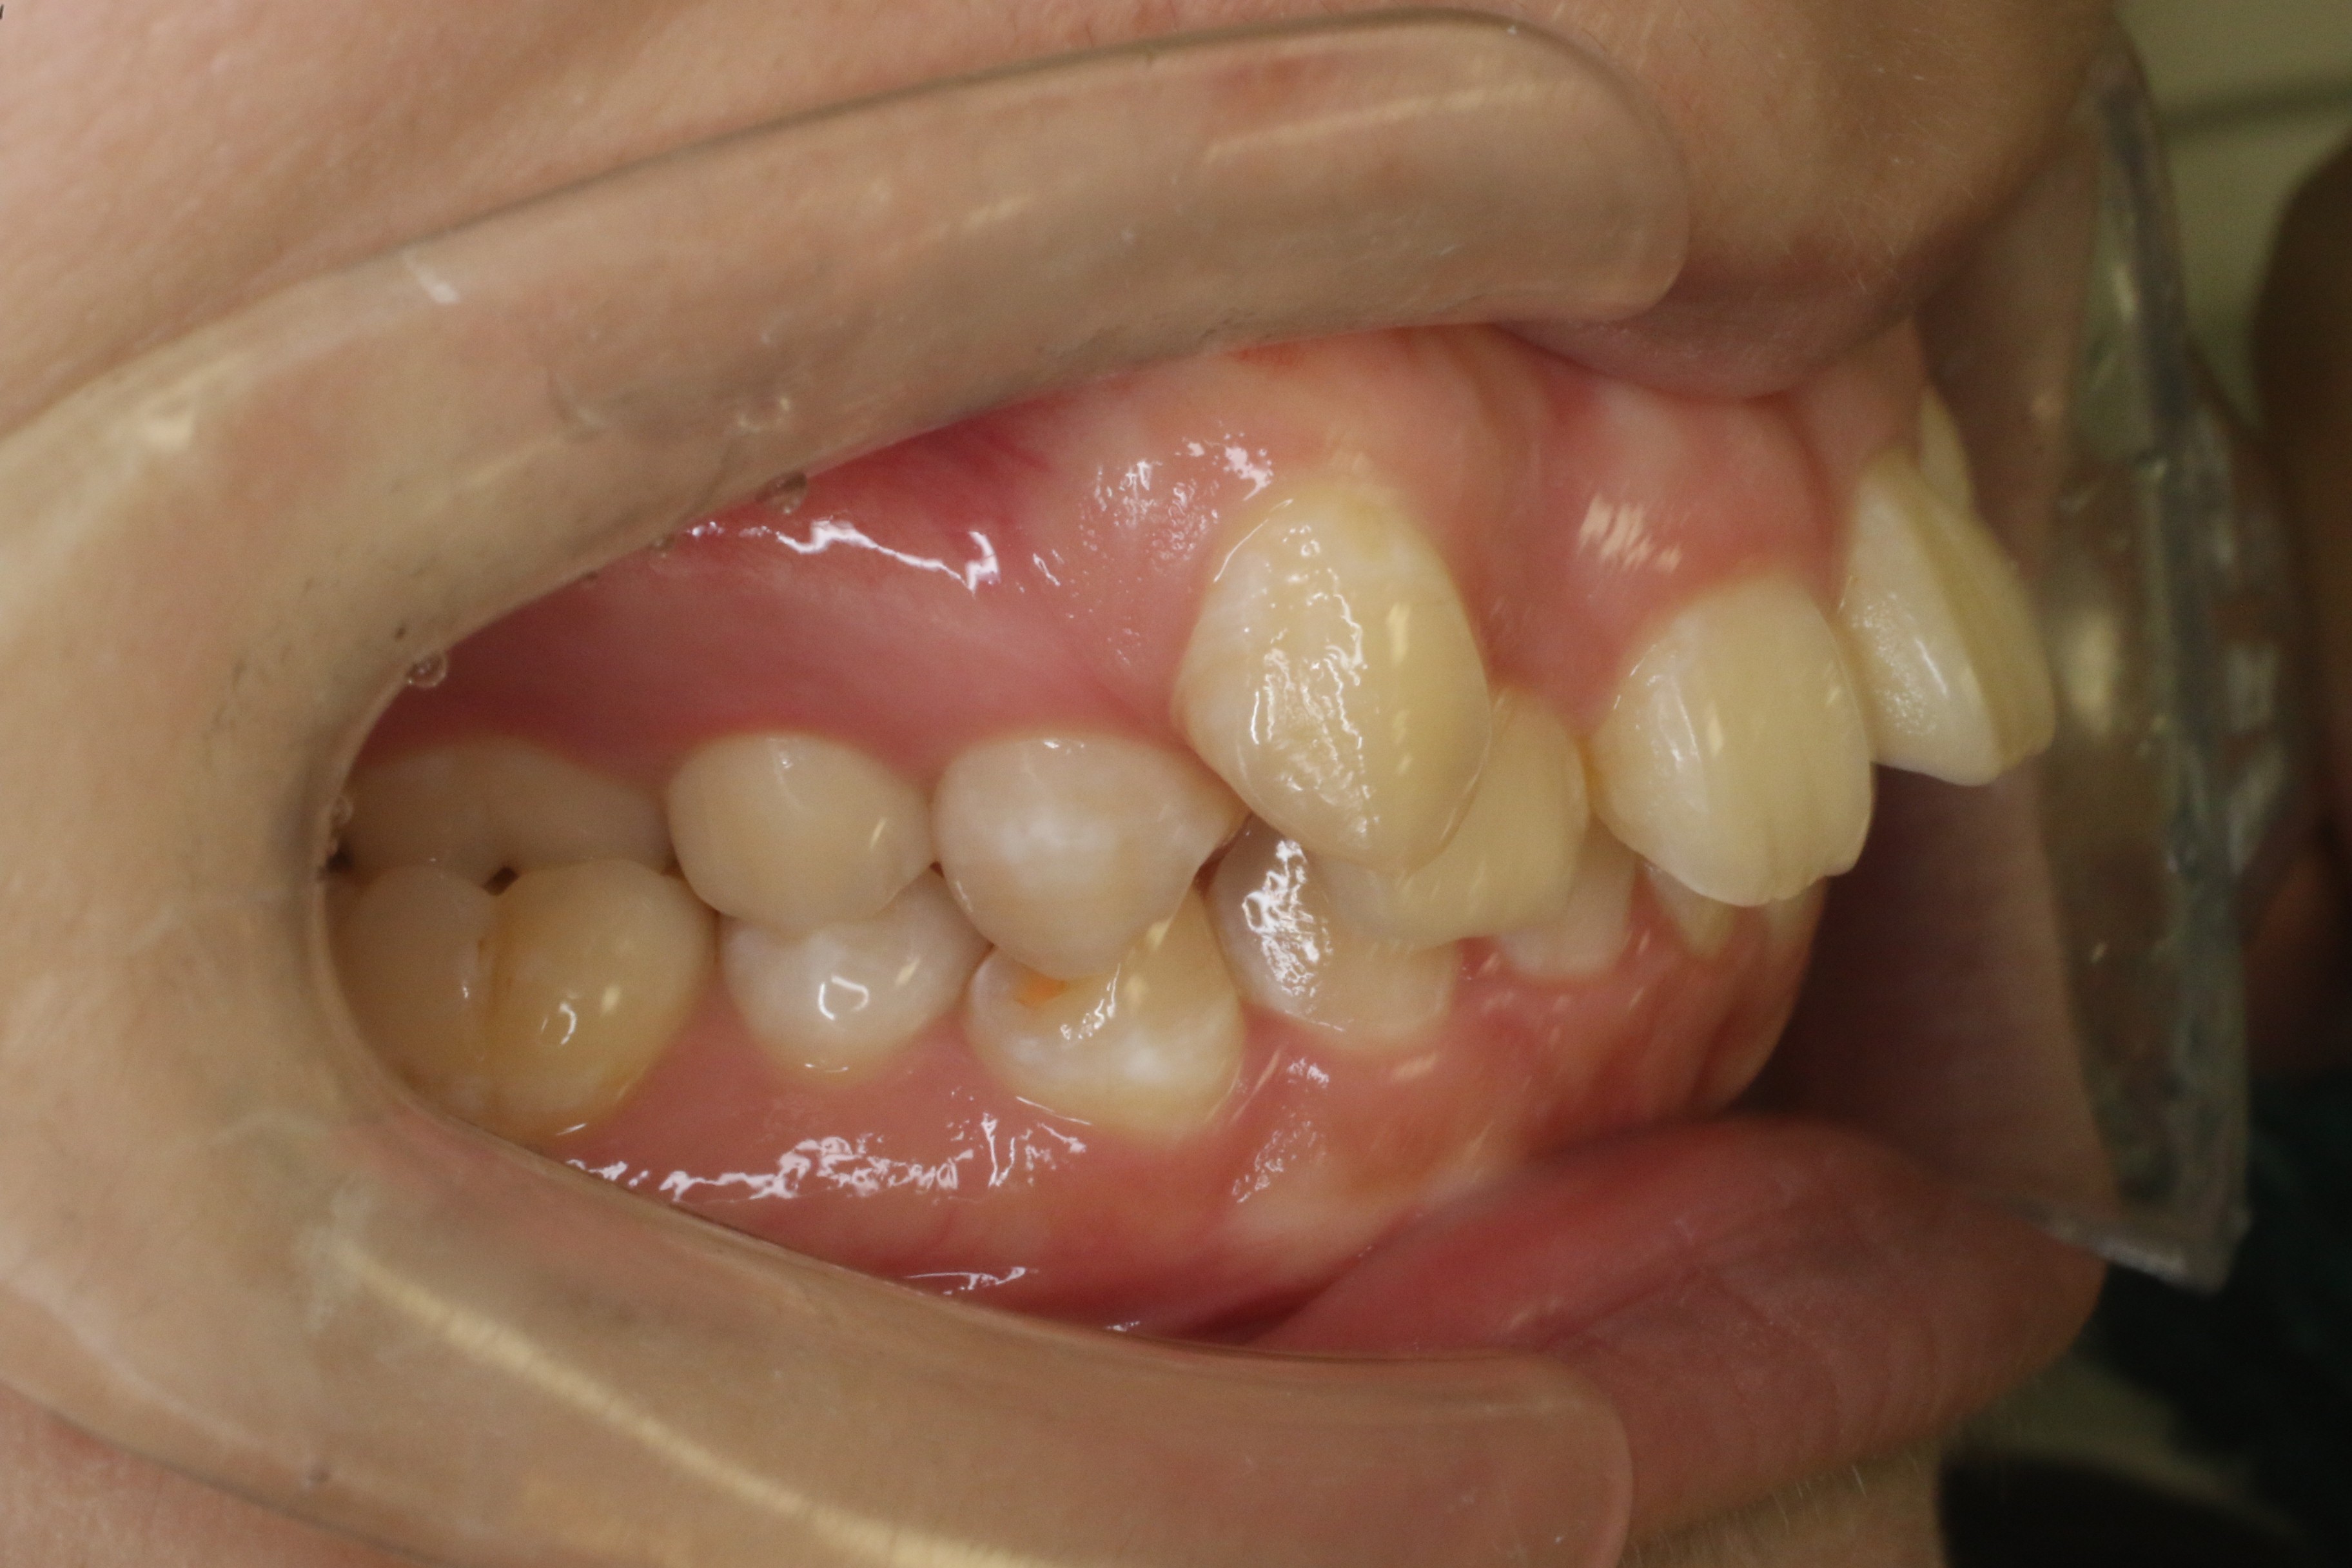

歯のデコボコを治したい

年齢層 20代

性別 女性

主訴 【主訴】歯のデコボコを治したい 【診断・症状】上下凸凹

治療費用 検査・診断:38,500-/裏側矯正治療:1,397,000-(※全て税込)

治療期間 約3年半(45回)

抜歯 有(上4,4、下 4,4)

矯正の装置 裏側矯正(舌側矯正)

副作用、リスク 歯肉退縮,歯根吸収,疼痛,咬合の違和感,装置の違和感,虫歯,歯肉炎